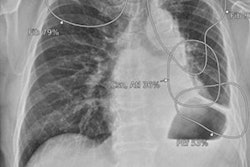

Process to estimate optimal depth of endotracheal tube using machine-learning model. (A) Acquire the recorded value of (a) fixed endotracheal tube depth from the electronic medical record and measure the distance from the carina to the tracheal tube tip (b) on the chest x-ray. Then, assume that the median of the distance from the carina to the upper margin of T1 and the distance from the carina to the lower margin of T3 is the optimal tracheal tube tip position (o). Finally, the ETT optimal depth value is derived by moving (a) as much as the distance that (b) has moved to the position of (o). Image courtesy of Scientific Reports through CC BY 4.0.According to the findings, the rate of inappropriate ET location was significantly lower using the machine-learning model (17.9%) compared with formula-based methods (35.7%, 62.2%, and 46.6%), the researchers reported.